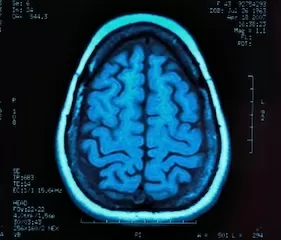

التصوير بالرنين المغناطيسي (MRI) هو اختبار طبي مشابه للأشعة السينية ، لكن التصوير بالرنين المغناطيسي يستخدم نبضات تردد الراديو ومجالًا مغناطيسيًا لإنتاج الصور بدلاً من الإشعاع. تظهر الصور على شاشة الكمبيوتر ويمكن طباعتها أو نقلها إلكترونيًا أو وضعها على قرص مضغوط.

تم استخدام إجراء التصوير لتحديد تلف الدماغ والأورام ، وهو أداة شائعة في العديد من دراسات التوحد أيضًا. قد يكون اختبار التصوير هو النهج الواعد للكشف المبكر عن التوحد.